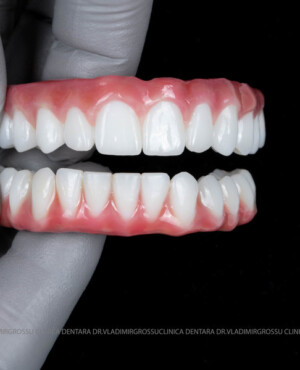

Pentru protezarea definitivă:

- Șase abutment-uri permanente pe multiunit-uri;

- Proteză definitivă realizată din metaloceramică sau zirconiu, cu 12-14 unități (soluția recomandată).